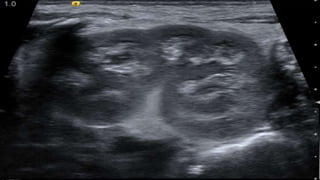

Fetal circulation

Postnatal transition and congenital heart defects